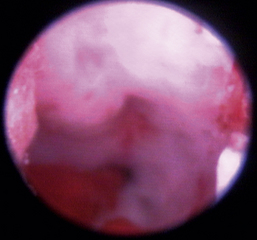

Normal turbinates have a smooth, pink-to-white surface and a spatial alignment that provides channels for the passage of air. The color varies and appears tan in the caudal nasal cavity. Turbinates come in different shapes and sizes, but the surface should be smooth. Ethmoid turbinates in the caudal nasal cavity will have a characteristic stippled or corrugated appearance (Figures 19-13 through 19-16). Ulcerations or various proliferations of the mucosa are indicative of disease. These changes are typically diffuse and accompanied by a lot of mucus. Mucus can be thin to purulent. Copious amounts can be flushed out of the nasal cavity to allow better visibility. The specific disease is determined by biopsy. After full examination of the nasal cavity, run the scope along the floor of the nasal sinus to the level of the choanae. Keeping the scope pointed in a ventral medial direction prevents inadvertent trauma or penetration of the cribriform plate. The index finger of the free hand can be used to follow the scope as it moves caudally over the hard palate; the surgeon can then palpate the scope through the soft palate when it moves into the nasopharynx. Some force is needed to complete this procedure and may result in increased bleeding.

image

Figure 19-13 Normal canine rostral nasal cavity; the septum is medial (left).

Figure 19-14 Normal canine meatus division.

Figure 19-15 Normal canine nasal turbinate mucosa.

Figure 19-16 Normal canine ethmoid turbinate.